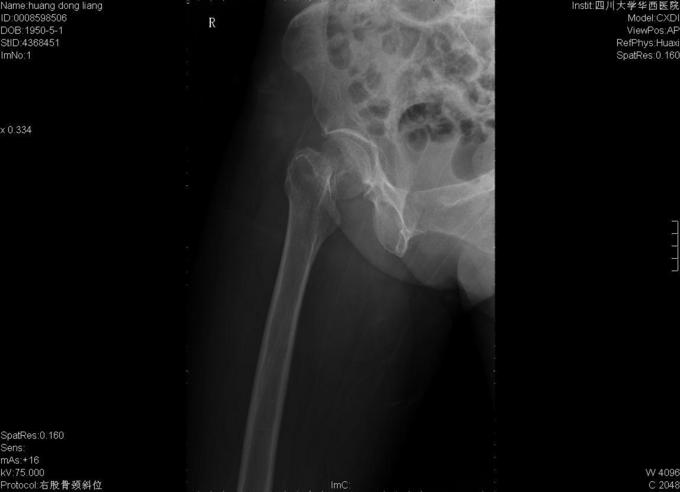

患者女,70岁,因"摔伤后右髋部疼痛、活动障碍10小时"入院,患者诉10小时前在家不慎滑倒,当即感觉右髋部疼痛、活动障碍,于当地医院急诊检查示:右股骨颈骨折,为求进一步诊疗故来我院。

查体:右髋部略水肿,右髋关节活动受限,不能负重。右髋部压痛(+),纵向叩击痛(+)。右髋关节活动受限,右膝及踝、足趾诸关节活动正常。 辅查:X线片示右股骨颈骨折,断端分离、错位。

入院诊断:右股骨颈骨折 诊疗计划:择期手术治疗,行右侧全髋关节置换。